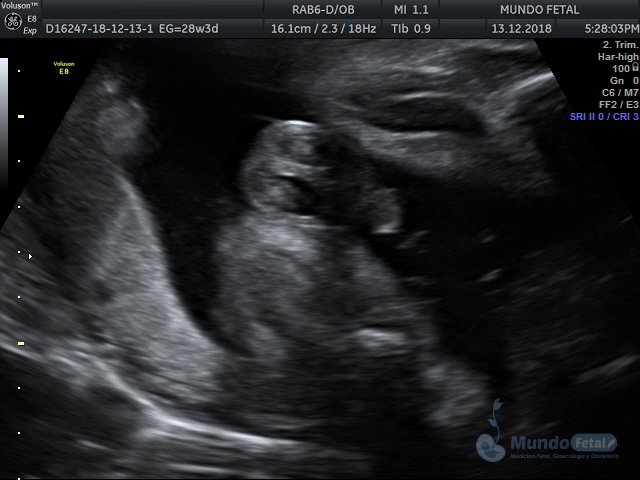

Mediante esta técnica ultrasonográfica, evaluamos en tiempo real al bebe y monitoreamos electrónicamente la frecuencia cardiaca fetal, vigilando los siguientes parámetros:

A cada parámetro se le asigna un puntaje basado en una escala del 0 al 10. Se ha propuesto que en estados fetales alterados por disminución del oxígeno se alteran los parámetros de manera que podemos predecir el estado fetal evaluando estos puntos.